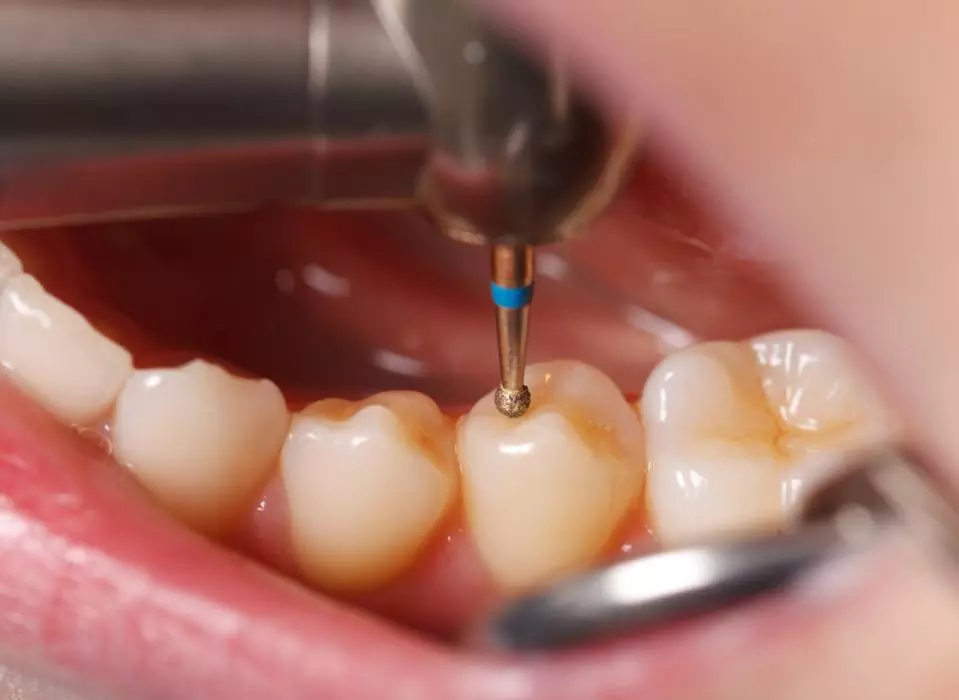

با جدیدترین روش های روز دنیا

با جدیدترین روش ها و ابزار های دنیا سلامت دهان و دندان خود را به ما بسپارید